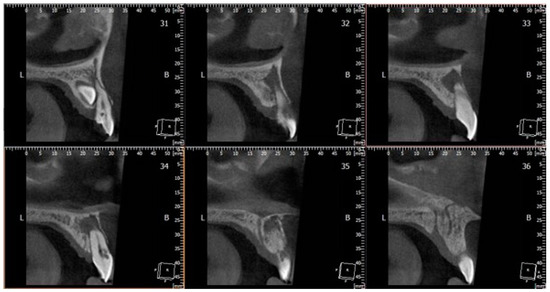

2. Case Report

- Patel, K.; Mannocci, F.; Patel, S. The Assessment and Management of External Cervical Resorption with Periapical Radiographs and Cone-beam Computed Tomography: A Clinical Study. J. Endod. 2016, 42, 1435–1440. [Google Scholar] [CrossRef] [PubMed]

- Patel, S.; Foschi, F.; Mannocci, F.; Patel, K. External cervical resorption: A three-dimensional classification. Int. Endod. J. 2018, 51, 206–214. [Google Scholar] [CrossRef]

- Vaz de Souza, D.; Schirru, E.; Mannocci, F.; Foschi, F.; Patel, S. External Cervical Resorption: A Comparison of the Diagnostic Efficacy Using 2 Different Cone-beam Computed Tomographic Units and Periapical Radiographs. J. Endod. 2017, 43, 121–125. [Google Scholar] [CrossRef]

- Ren, H.; Chen, J.; Deng, F.; Zheng, L.; Liu, X.; Dong, Y. Comparison of cone-beam computed tomography and periapical radiography for detecting simulated apical root resorption. Angle Orthod. 2013, 83, 189. [Google Scholar] [CrossRef] [PubMed]